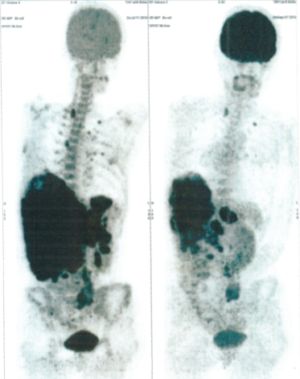

Below are some of the cases, from more than 80 cases we have treated so far with good results. When reading the PET/CT scans, the picture on the left is before treatment, and the picture on the right is after treatment. The intensity of black represents the activity of the cancer, but some black areas are not cancer: brain, heart, radioactive urine in bladder. For the heart, the intensity of black depends on the number of hours of fasting: if more than 10 hours, the heart is not even black, but if fasting is less than 6 hours, it is very black. The intensity of black in the brain can be variable in different scans depending on the brain activity at the time of the scan. The intensity of black in the radioactive urine can also be variable due to the hydration of patients and the time of injection of diuretic.

CASE NO: 1

(HEPATOCELLULAR CARCINOMA + STOMACH CANCER)

A middle-aged women who is very thin and very weak, can hardly walk, lying in bed most of the time. She saw a cancer specialist in a top hospital who discovered that she had massive hepatocellular carcinoma, and another cancer in the stomach. Given that hepatocellular carcinoma is incurable and stomach cancer is very difficult if not impossible to cure without surgery, she was told that nothing could be done for her. She came to ask us to help her. After just 4 treatment, the hepatocellular carcinoma went into remission, and the stomach cancer (arrow) became less active. Until today, more than 6 months later, the hepatocellular carcinoma is still in remission.

CASE NO: 1 - A FEW MONTHS LATER

A few months after successful treatment for hepatocellular carcinoma, and partially successful for stomach cancer, the PET/CT scan showed the stomach cancer becoming very active, with several metastases to the parts of the liver not previously involved by hepatocellular carcinoma. After a few treatment, all the active stomach cancer lesions in the stomach and in the liver went into remission.